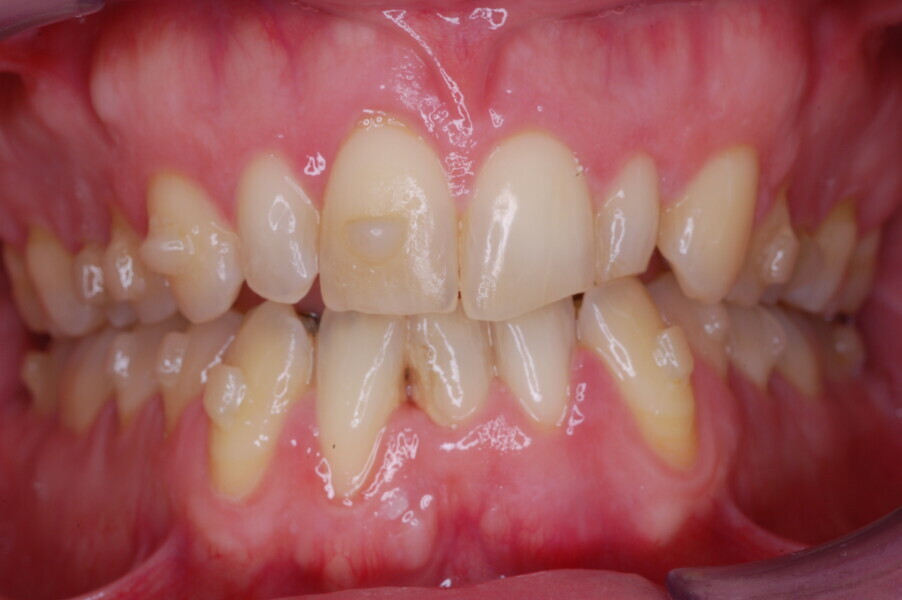

A healthy 39-year-old man presented to our orthodontic office with the chief complaint of an unattractive dental appearance and fear of the orthognathic surgery proposed by another orthodontist. Clinically, the patient’s profile was straight, and the frontal view did not show any facial asymmetry. The functional examination did not reveal any mandibular deviation or reduced movements. The patient had no joint pain, and no joint noise was observed.

Figs. 1–8: Pretreatment facial and intra-oral photographs.

From the periodontal point of view, the patient showed a good attitude to oral hygiene, but crowding of the mandibular incisors made cleaning difficult in that area, causing plaque accumulation and localised gingival inflammation. The panoramic radiograph revealed the presence of the mandibular third molars and confirmed the absence of the mandibular right central incisor (Fig. 10).

The cephalometric analysis showed a skeletal Class II malocclusion (convexity of Point A: 4.9 mm), a slightly retruded chin position (facial depth: 78.1°) and a skeletal open bite tendency (lower facial height: 53.19°; facial axis: 80.58°; Fig. 9). The mandibular incisors were lingually tipped (Li–APog: 9.3°) and retruded (Li–APog: 1.55 mm), and there was an increased inter-incisal angle of 142.9°.